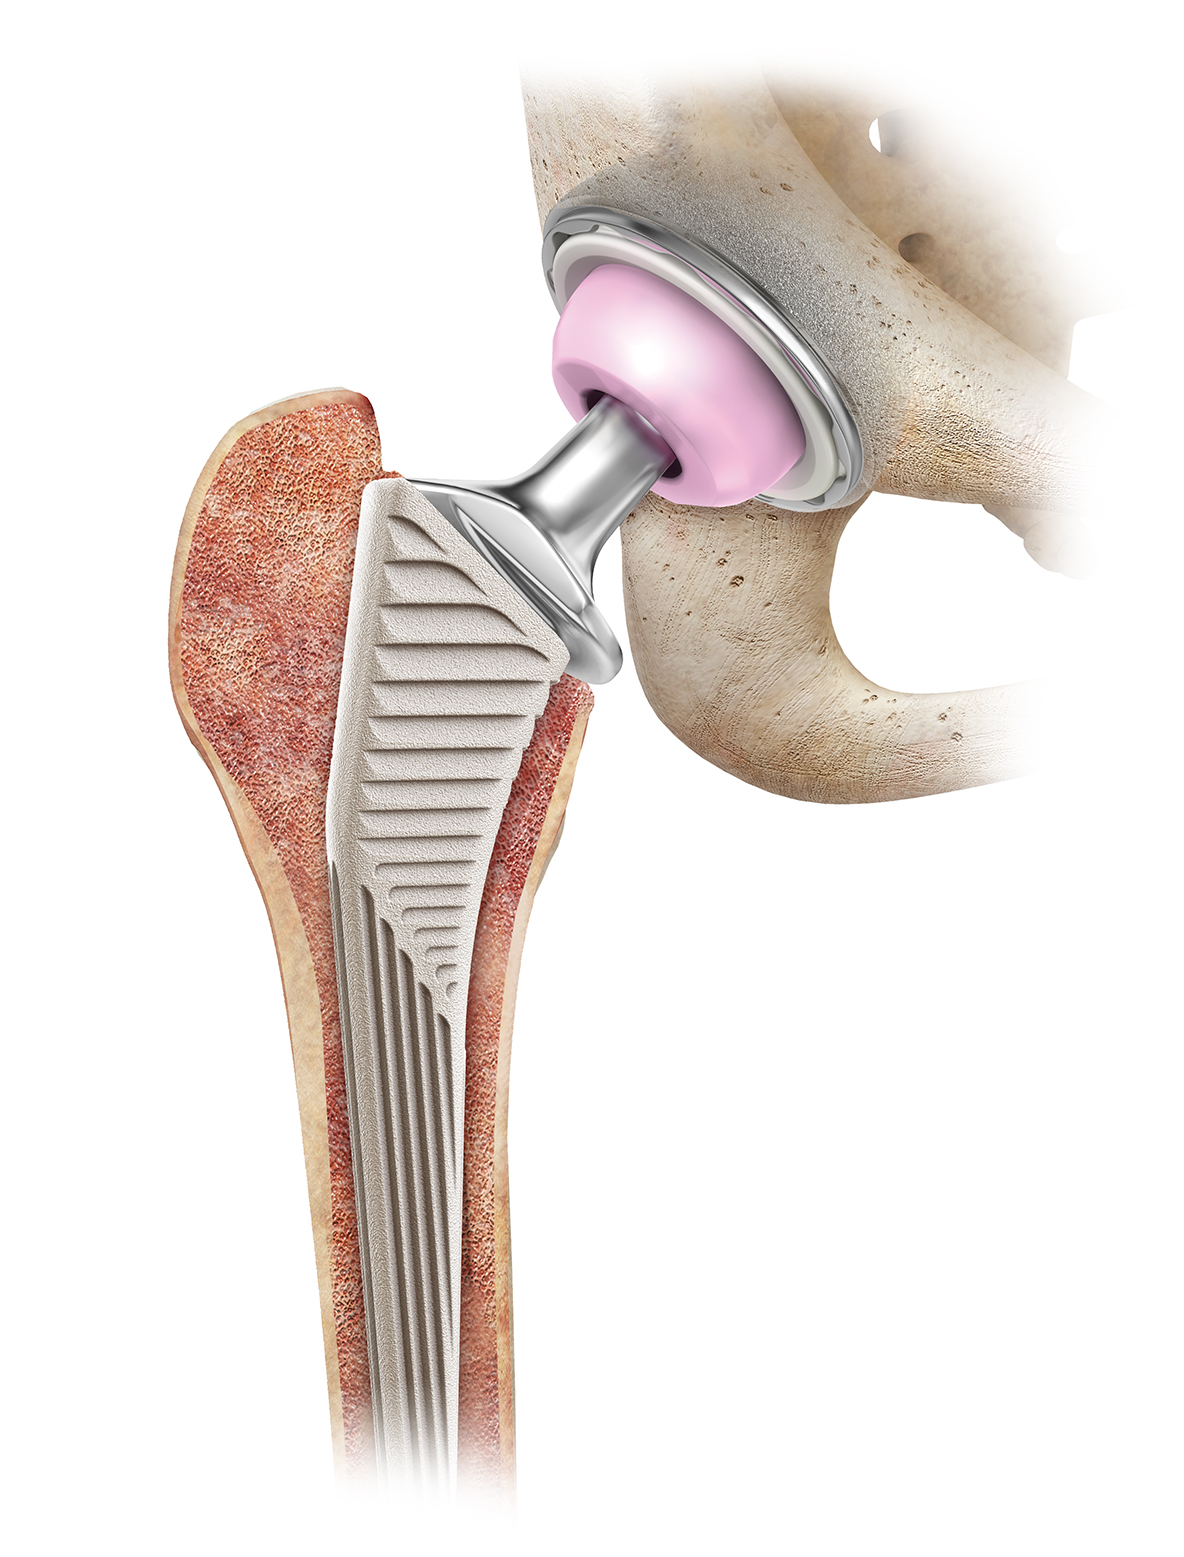

Total Hip Replacement BJISG

http://bjisg.com/wp-content/uploads/CoP_collar_in_bone_Web.jpg

Total Hip Replacement Hip Osteoarthritis

Total Hip Replacement Surgery At UPMC Sports Surgery Clinic